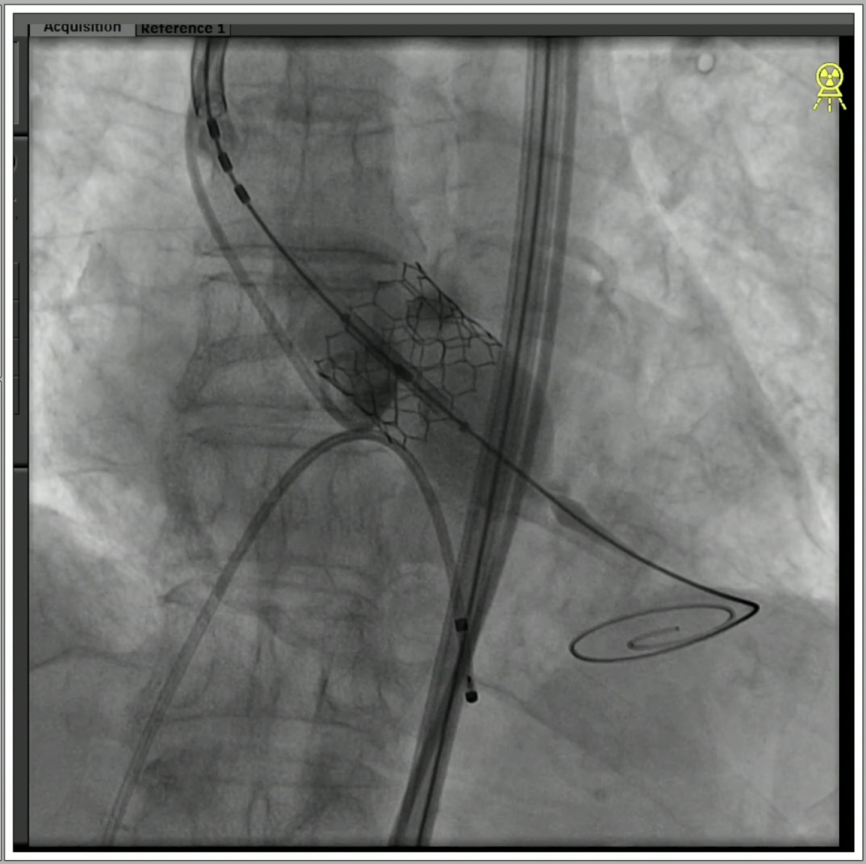

3、使用20mm球囊进行预扩,无腰征无反流,两侧钙化被球囊推开。

4、通过支撑导丝,送入23mm SAPIEN 3瓣膜,使用独特调弯功能,保证安全过弓并成功跨瓣;

5、调整至共平面角度,瓣膜到位,快速起搏下精准释放瓣膜。

6、瓣膜植入且撤出导丝后,造影超声结果均显示瓣膜工作良好,术后导管测量压差8mmHg,经胸超声检测微量瓣周漏,手术成功。